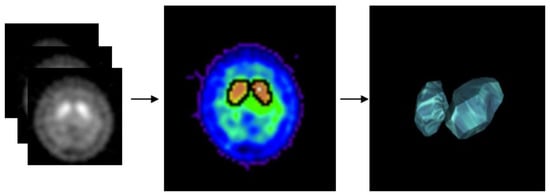

1. Introduction

2. Materials and Methodology

2.3. Experimental Design